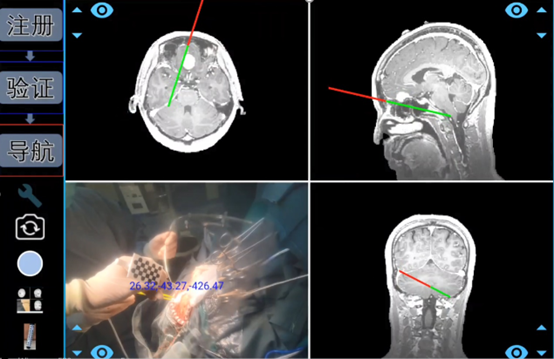

借助深度相机,综合深度学习和视觉算法,该系统能实现虚拟空间和现实空间的高精度一键配准,将生成的3D“透明脑”1:1与病人实际情况进行匹配, 进行术中导航。

(术中导航)

试验数据显示,其配准精度可达亚毫米级。算法能力的提升,可将传统手术导航的配准时间由传统的近半个小时,缩短至几秒钟,为病人抢占宝贵的治疗时机。